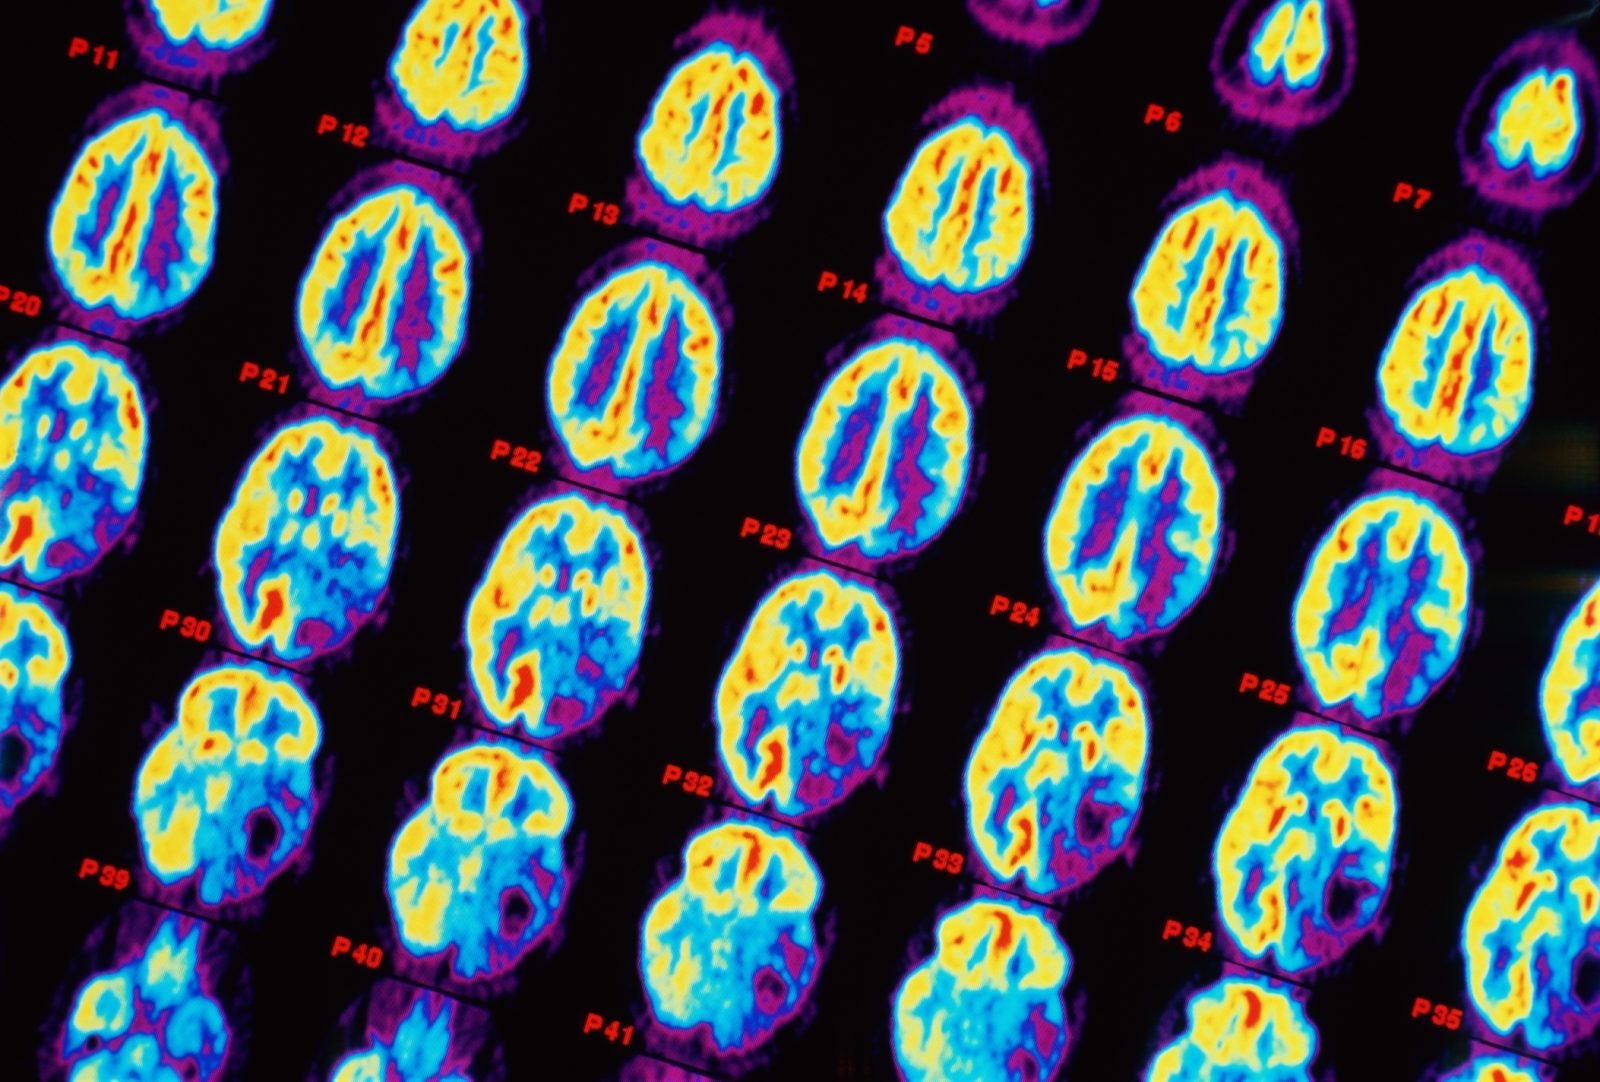

Pozytonowa tomografia emisyjna (PET) to technika obrazowania, w której zamiast zewnętrznego źródła promieniowania rentgenowskiego lub radioaktywnego (jak w tradycyjnej tomografii komputerowej), rejestrowane jest promieniowanie powstające podczas anihilacji pozytonów (antyelektronów). Technika ta jest uważana za jedno z największych osiągnięć w diagnostyce nowotworów, pozwalającą na skuteczne namierzanie komórek rakowych.

W PET wykrywa się podwyższony metabolizm glukozy w komórkach nowotworowych (pochodzący od analogu glukozy – fludeoksyglukozy, FDG). Zazwyczaj zmiany te można wykryć jeszcze przed wystąpieniem objawów w innych badaniach diagnostycznych. PET najlepiej sprawdza się w badaniu chłoniaków, raka płuc, nowotworów głowy i szyi. W niektórych przypadkach technika ta może okazać się skuteczna w diagnozowania raka prostaty, a także przerzutów do mózgu lub kości.